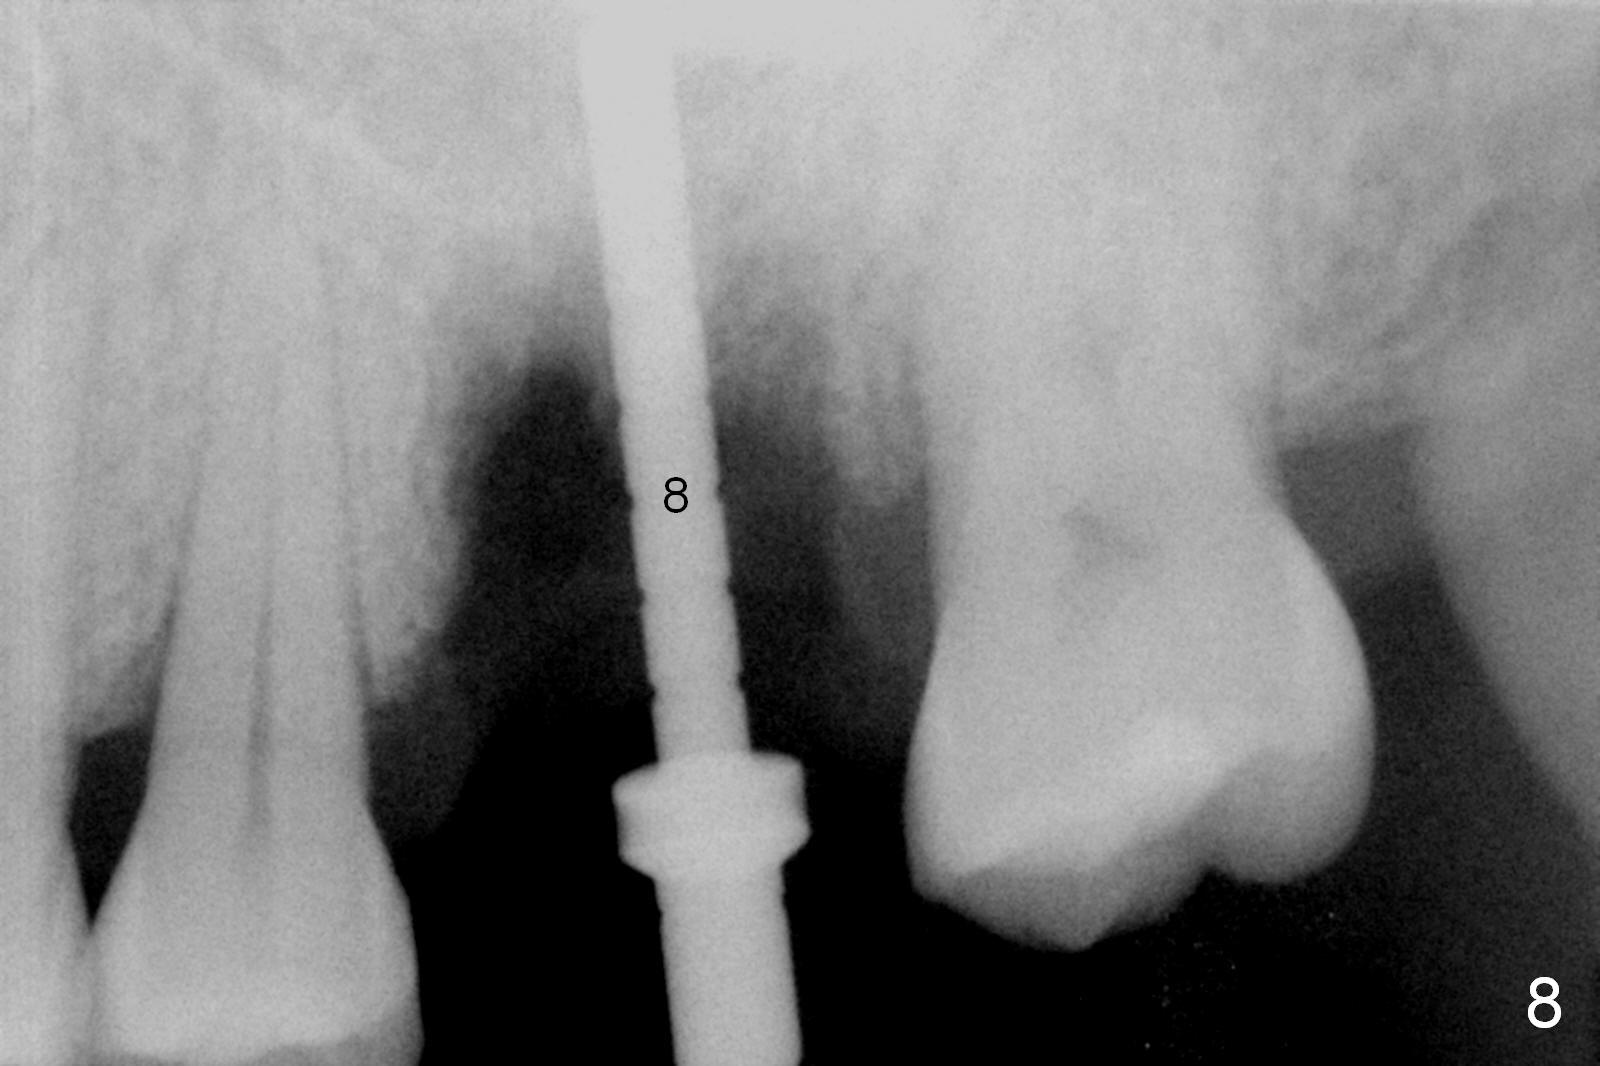

Osteotomy is initiated in the palatal slope of the septum 8 mm deep (Fig.8,9). A 5x11.5 mm implant is placed with insertion torque of 35 Ncm with ~ 2 mm sticking into the sinus with bone graft and 1.5-2.5 mm outside the septum. The latter is covered by bone graft (Fig.10 *). There is no nasal hemorrhage postop.